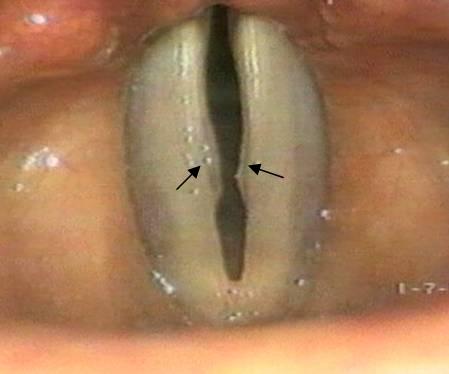

人的聲音是由氣管最上方特化之聲帶所發出的,左右各一,成人聲帶的平均長度為男生:1.6公分、女生:1.2公分。左右聲帶前方相接,後方則為可活動之關節。平常時聲帶處於打開之狀態,以利呼吸之空氣進出氣管。說話時喉部肌肉收縮,讓兩側聲帶靠近(圖1),而後經由肺部呼出的氣流震動兩側聲帶而發出聲音。瞭解了聲帶的結構之後,我們不難理解聲音的品質是決定於以下幾個因素,缺一不可。1)兩側聲帶的活動性,能否緊閉 2)聲帶表層是否平整、對稱 3)聲帶皮下層是否柔軟,讓聲帶波很平順的由下而上、由裡而外的傳遞開來。

(箭頭所指即為聲帶結節)

聲帶長繭常見於職業上需要長期說話者,如歌手、老師、業務員、零售攤販等。女性因為先天音調較高,聲帶較薄,出現聲帶長繭的機 會比男性高的多。上圖箭頭所指處為早期之聲帶結節,可見聲帶表皮略微增厚。若持續過度使用聲音,則會逐漸惡化,出現聲帶充血、水腫且出現不正常之血管紋等變化。